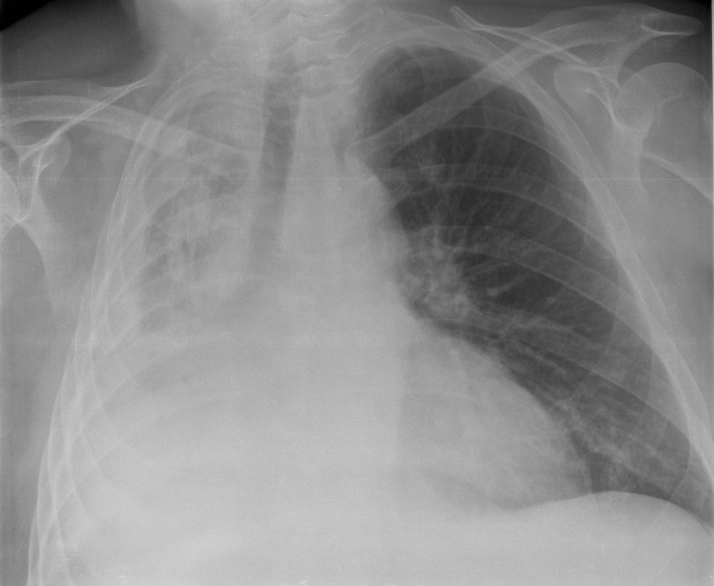

CXR Pattern Examples (Quick Look)

Pneumothorax on CXRWikimedia Commons

Pleural effusion on CXRWikimedia Commons

Lobar pneumonia on CXRWikimedia Commons

ARDS on CXRWikimedia Commons

Atelectasis on CXRWikimedia Commons